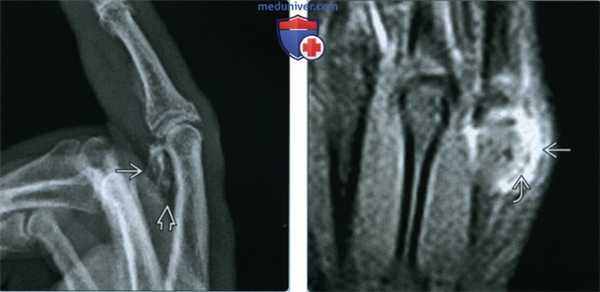

(Левый) Рентгенография в боковой проекции: оссифицированное объемное образование, залегающее по ходу ладонного отдела проксимальной фаланги 2-го пальца кисти. Визуализируется не выраженная «плоскость скола» между объемным образованием и смежным кортикальным слоем кости.

(Правый) МРТ, STIR, корональный срез: объемное образование с высокой интенсивностью сигнала и частично окружающее дисталь -ные отделы 5-й пястной кости. На этой последовательности нечетко определяется образование В, прилежащее своим основанием к поверхности кости. Признаки образования неспецифичны и могут свидетельствовать как о новообразовании, так и о инфекционном поражении/травме.